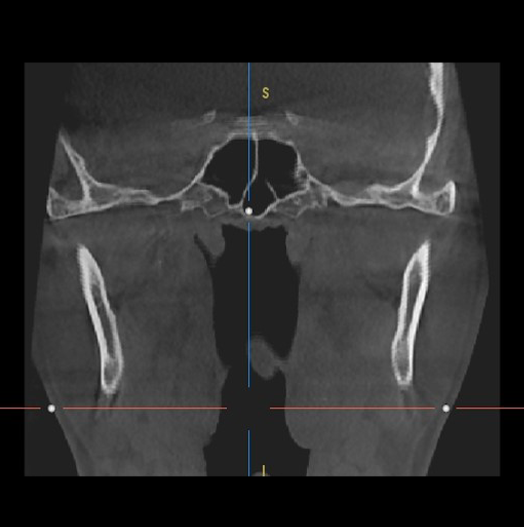

(Smart Metal Artifact Reduction Function)

Metal artifactを最小化し、補綴物による映像品質の低下を防ぎ、

最適な映像を提供します。